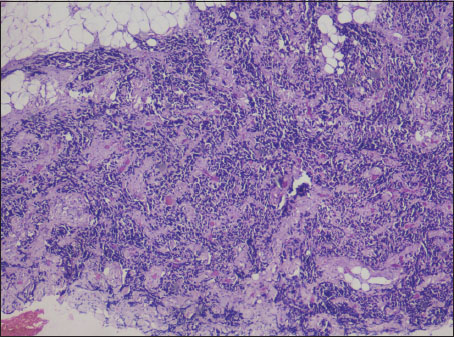

An incisional biopsy was taken from the right labial vestibule and submitted for histopathological examination. The findings showed connective tissue stroma with a dense, homogenous proliferation of small round to oval blue cells. These cells were arranged in sheets and strands separated by connective tissue septa. The cells showed a round to oval basophilic, hyperchromatic nucleus surrounded by a scanty rim of cytoplasm which was inconspicuous [Figure 5].

| Figure.5:The H and E picture shows sheets of densely arranged small round cells with hyperchromatic nuclei invading the adipose tissue (magnification, ×4)

Ewing's Sarcoma (ES) is exclusive in the bone. PNET has been termed as the extraskeletal variant of ES. EES is also similar to PNET as arising in the soft tissues but does not have the typical neural differentiation which forms the differentiating factor between them.[11] The histopathologic features of EES includes sheets of small round cells (included under Small Round Cell Tumors) with a uniform hyperchromatic nucleus and scanty cytoplasm. A variant termed as Atypical Ewing's sarcoma is seen wherein the monomorphic round cells are replaced by atypical-shaped cells with a hyperchromatic nucleus and scanty cytoplasm The clinical features of atypical Ewing's sarcoma resemble lymphomas, carcinomas, and sarcomas but the molecular and immunohistochemical features are similar to that of ES.[12]